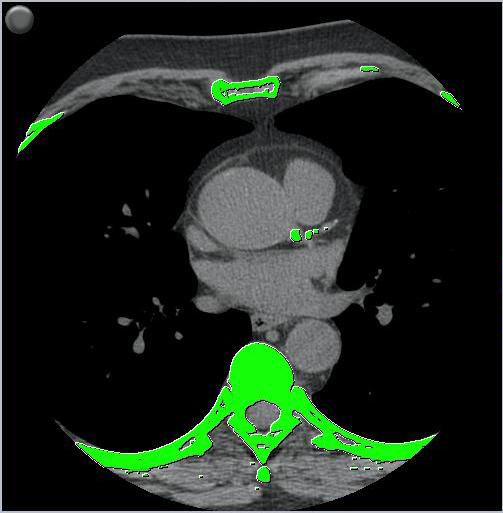

calcium score

syngo Calcium Scoring is an evaluation software used for quantifying calcified coronary lesions. The data is based on low dose (less than 1-2 mSv) acquisition with either ECG triggered sequence or retrospectively gated spiral scans. Multiple studies with conventional subsecond CT scanners have shown that the Calcium Scoring results can be used to closely follow changes in coronary calcium load.